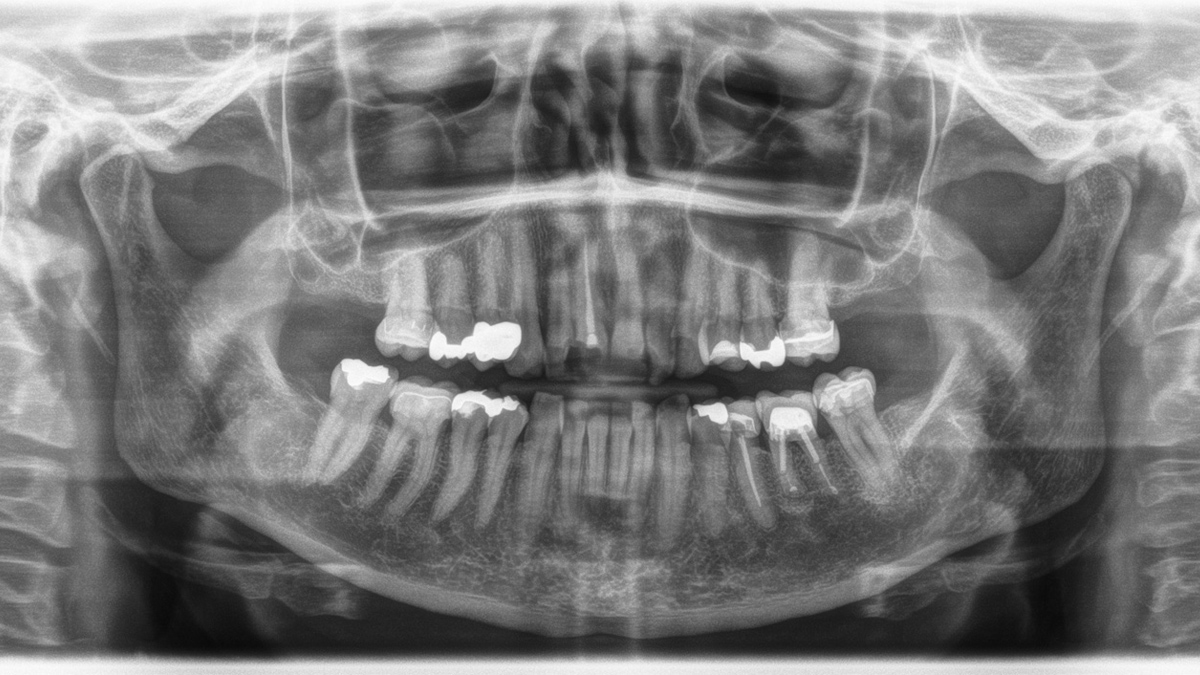

Prophylactically treated full dentition. Wisdom teeth are not present. Large maxillary sinuses are visually inconspicuous. The adjacent anatomical structures are also radiographically inconspicuous.